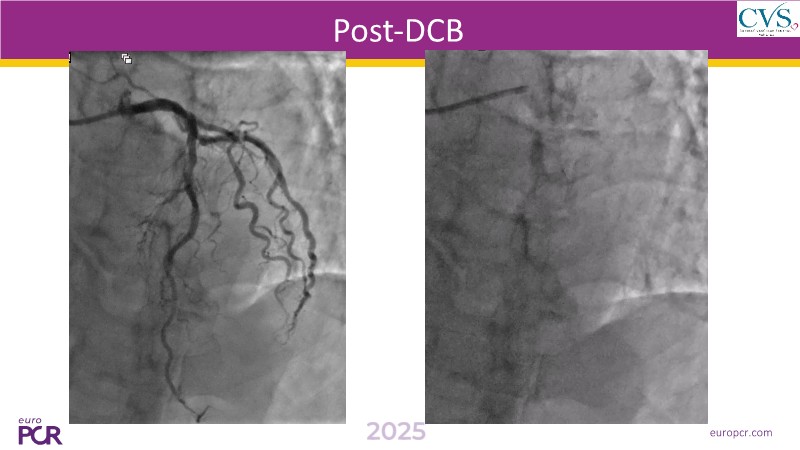

Discover how the next-generation RevoEdge high-pressure cutting balloon is transforming PCI with innovative design and proven clinical outcomes. This session presents a multicenter randomised trial and real-world case discussions, showcasing RevoEdge’s effectiveness in tackling resistant, complex lesions—including long, tortuous, and fibrotic cases. Learn practical tips, tricks, and intravascular imaging insights to optimize lesion preparation and improve patient outcomes. Don’t miss this opportunity to see how RevoEdge helps you cut through challenges and conquer PCI complexities.

- To learn about the clinical benefits and tips and tricks of using RevoEdge high pressure cutting balloon in different types of complex lesions through case-based discussion